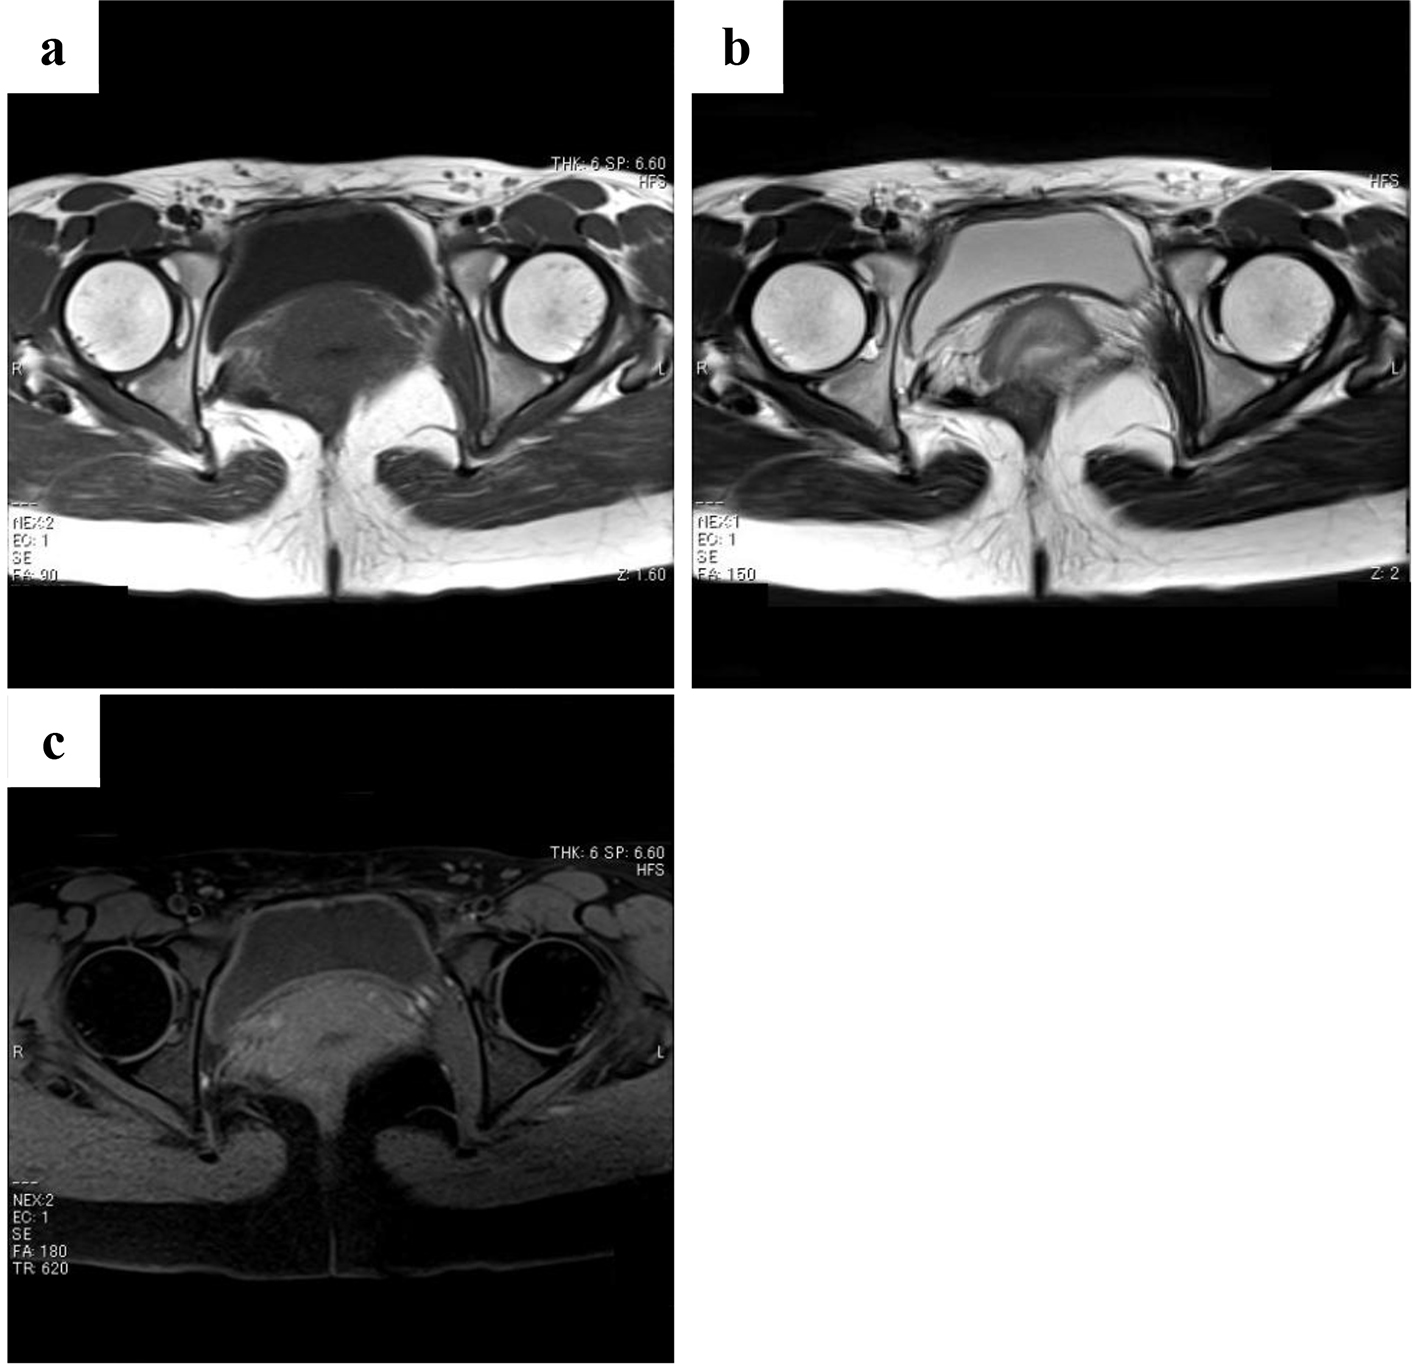

Figure 1. Magnetic resonance images obtained at first examination. There is an enhanced mass (8 cm in diameter) attached to the urinary bladder arising from the internal obturator muscle. The tumor shows a moderately low signal intensity comparable to skeletal muscles on T1-weighted images (a), a moderately high signal intensity on T2-weighted images (b), and high enhancement with a partially mottled pattern after intravenous administration of gadolinium contrast agent (c).